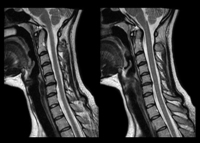

Magnetna rezonanca (eng. Magnetic Resonance Imaging), skraćeno MRI, je način snimanja Vašeg tijela bez korišćenja X zraka ili bilo kave radijacije. MRI aparat stvara slike koristeći magnetno polje koje se prirodno nalazi u našem organizmu. Magnetna rezonanca prikazuje meka tkiva tela (mišiće, nerve, mozak, pršljenske diskove, ligamente i td.). U mnogim situacijama magnetna rezonanca nudi jedinstvene informacije koje pomažu Vašem doktoru da odredi bolji plan terapije i nege.